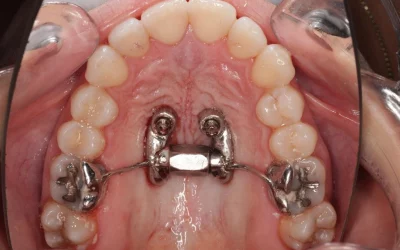

MARPE y alineadores: todo lo que debes saber para una correcta planificación

La expansión palatina asistida por microtornillos (MARPE) se ha convertido en una de las herramientas más potentes para corregir discrepancias esqueléticas transversales en adolescentes tardíos y adultos jóvenes. En una época en la que la estética y la comodidad...